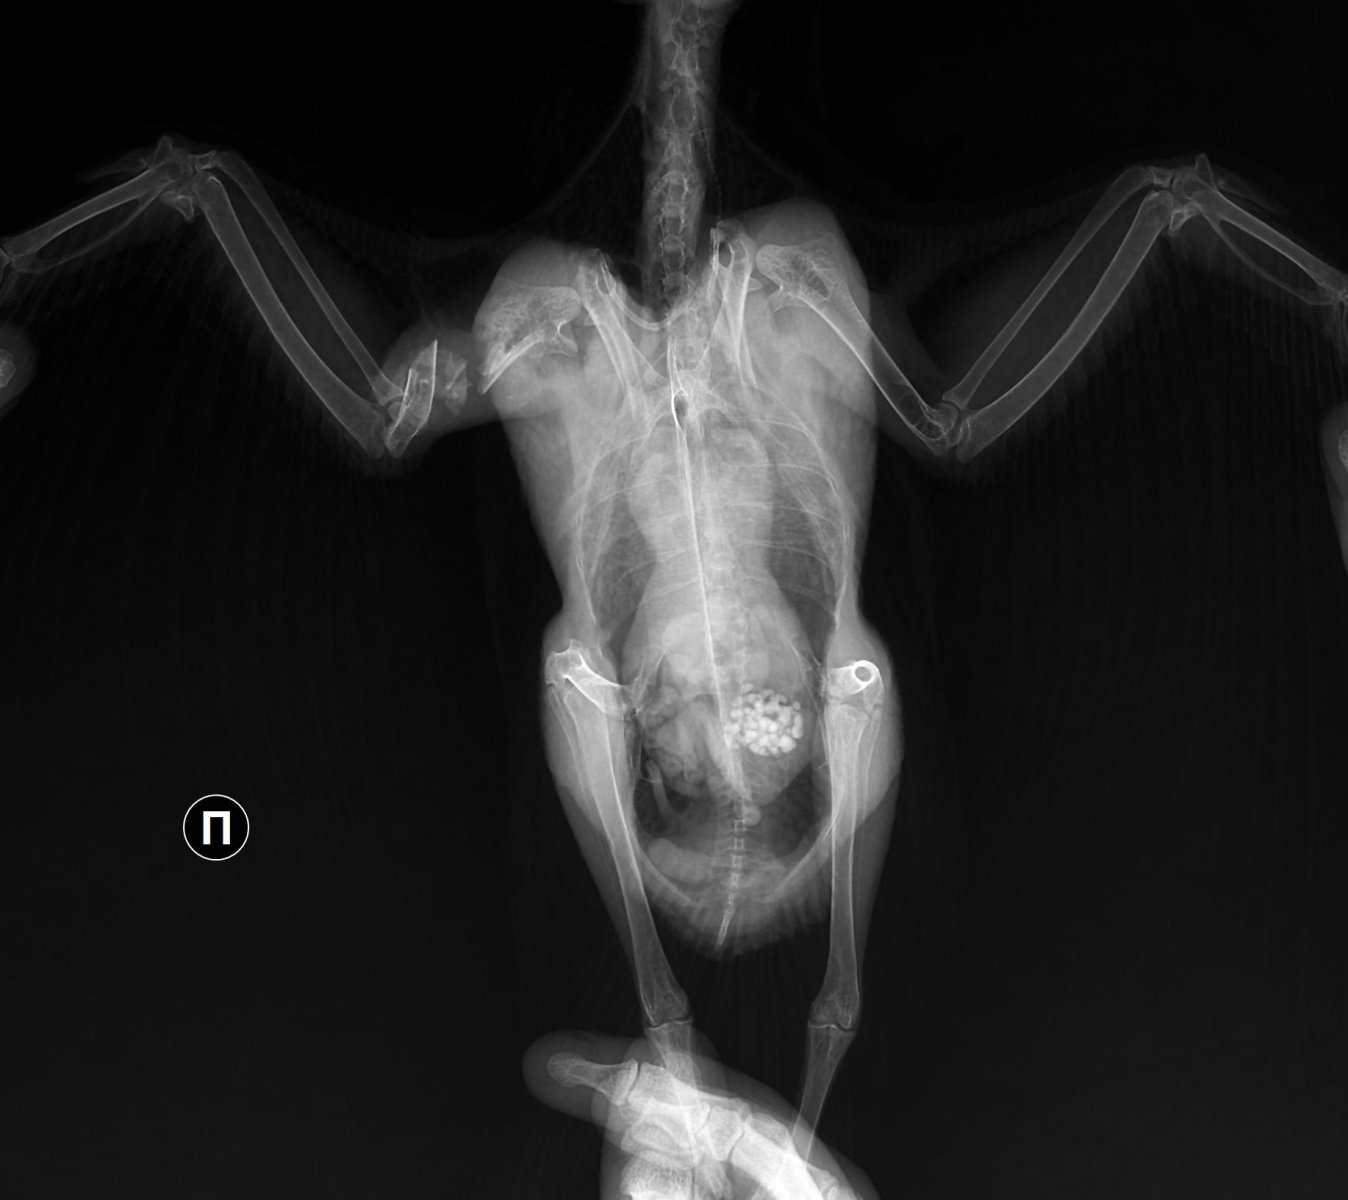

Рентген №1 - 08.121_3011977922r.thumb.jpg.1c03db7fd202f6f6e764bf55e9a4103d.jpg

1_3011977922r.thumb.jpg.1c03db7fd202f6f6e764bf55e9a4103d.jpg1_3011993622r.thumb.jpg.7575556377acddc5708415dfcdcf6558.jpg

Рентген контрольный - 22.12

1_3131795322r.thumb.jpg.d84909cef2a8ef1a6f8861285e32d1be.jpg1_3131813522r.thumb.jpg.2b83701bfbf4fd71082afc4022d192bd.jpg

Врач после второго рентгена говорила, что надежда ещё не потеряна, но скорее нет чем да, а если полетит, то не раньше чем через месяц. Прошло уже два, прогресс крайне мал (

Если представленные снимки свежие- то летать он не будет, т.к. за 3 месяца после аварии у него нет даже признаков консолидации или хотя бы образования ложного сустава.

на представленных снимках перелом полный , с чрезвычайно большим смещением всех отломков.  Если не производилась хоть какая-то репозиция отломков, то там нечему и некуда прирастать... там расстояние между частями отломков долее 5 мм, а то и все 8.

Снимки датированы - 08.12.22; 22.12.22